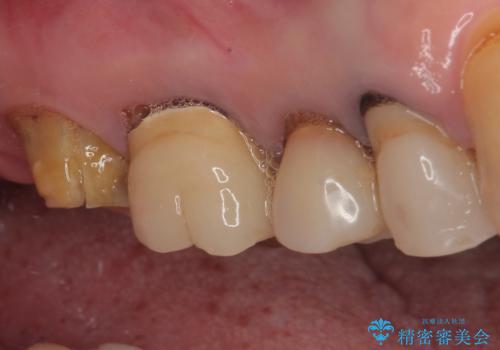

抜歯後2ヶ月でのインプラント埋入を行いましたが、骨の再生は不十分でした。

骨量は不十分でしたが、デンサーバーを用いることで無事に埋入することができ、その後は速やかに補綴治療を行うことができました。